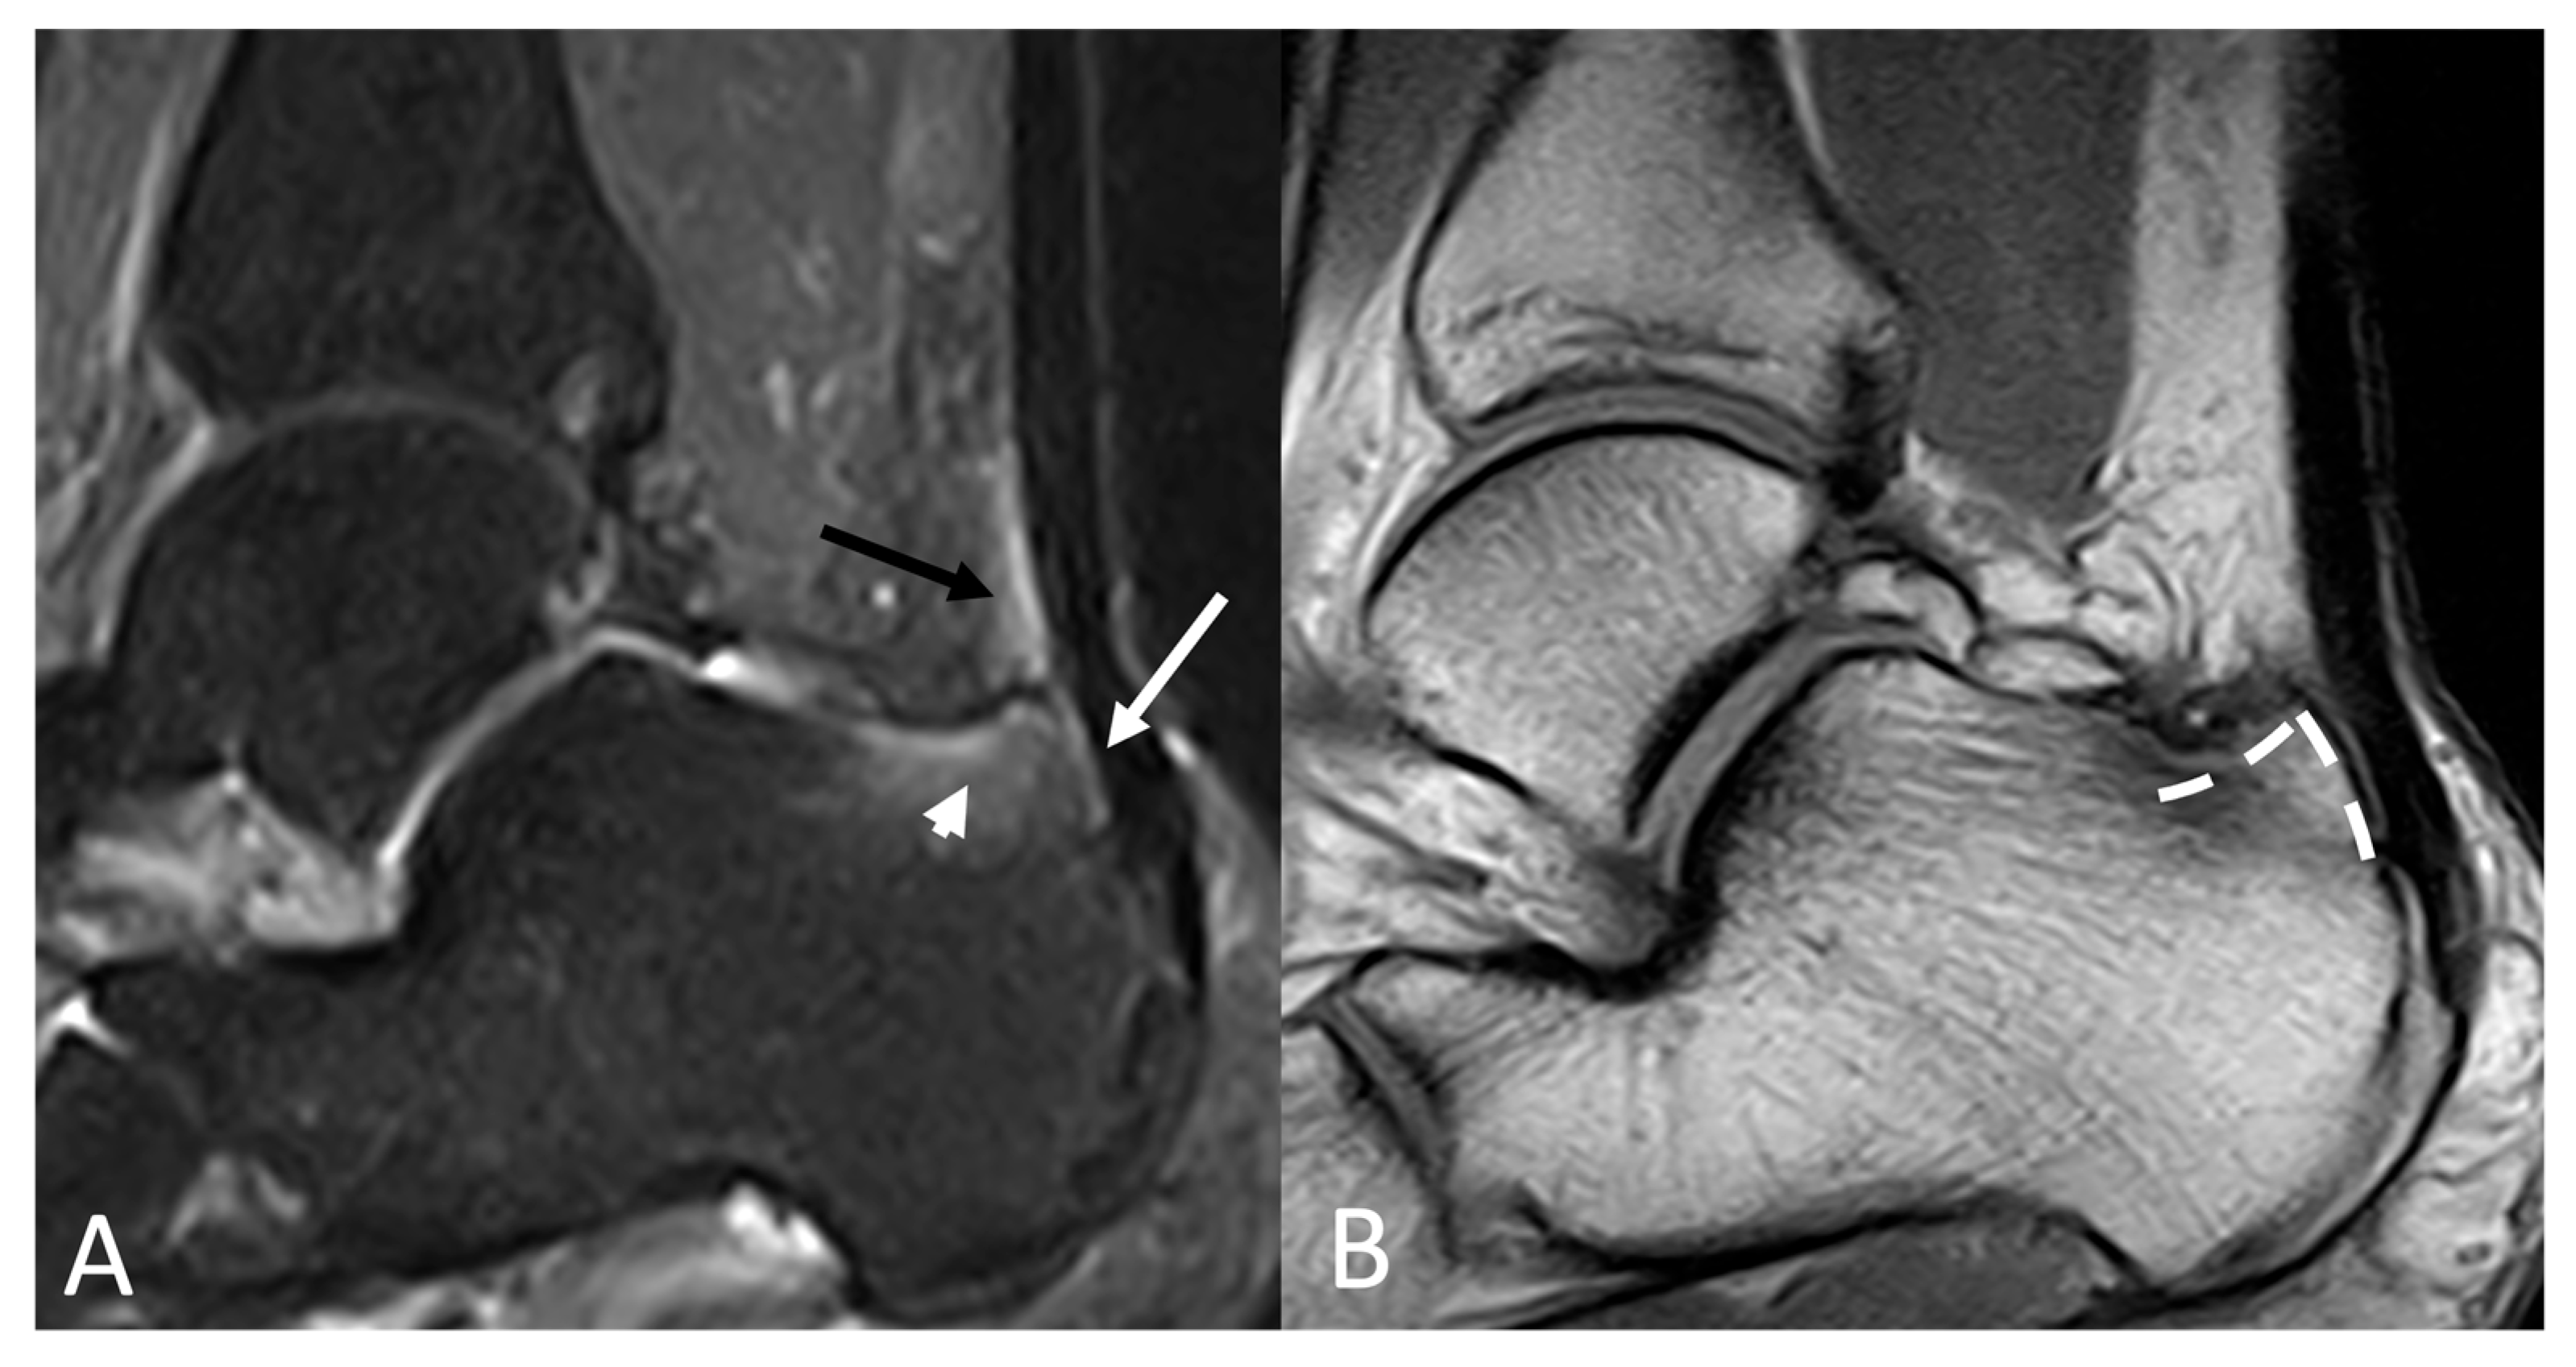

Haglund Deformity (HD) (Figure 8) is a condition characterized by an enlargement in the form of exostosis in the posterosuperior region of the calcaneal bone. Haglund’s disease refers to the constellation of conditions caused by HD, including Achilles tendinitis, retrocalcaneal bursitis, supracalcaneal bursitis, and inflammation of the Kager fat pad [34].

Figure 8.

(A) Sagittal STIR and (B) sagittal T1-weighted of a 37-year-old male with pain and a bump at the level of calcaneal insertion of the Achille’s tendon. Bony edema of the calcaneus (arrowhead) and the area of impingement between the bone and the tendon (arrow). Retrocalcaneal bursitis is evidenced by increased fluid and inflammation (black arrow). A bony bump on the posterosuperior calcaneus (dashed line) is present, consistent with Haglund’s deformity.

In both OSD and Haglund’s Disease, X-ray allows the detection of bone deformity, but MRI provides a more sensitive and specific assessment for soft tissue evaluation, including tendons, bursae, and fat pads (e.g., tendon, fat pad, bursae) [34,35,36].